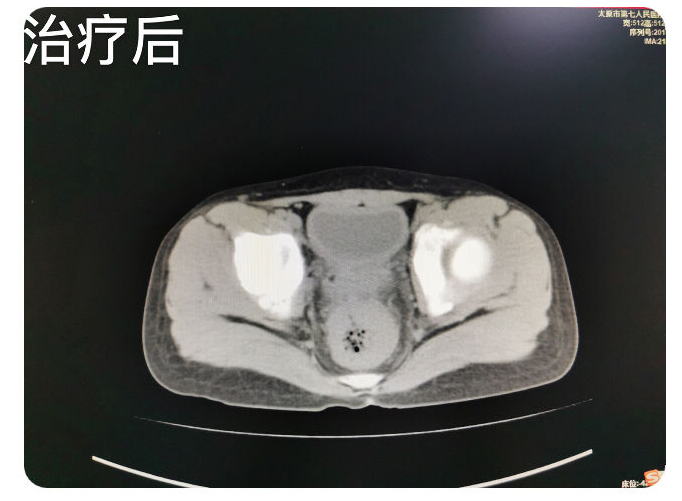

患儿九岁,主因排便控制不佳两月余,辗转就诊于省内多家二人麻将 ,未明确诊断,治疗效果欠佳,肛门失禁症状逐渐加重,患儿及家属均承受了极大的心理及经济负担,后来患儿家属慕名就诊于二人麻将指南网 翟春宝主任医师门诊。翟主任通过仔细询问病史,细致查体后,考虑为粪性嵌塞引起的肛门失禁。入院检查CT,确认患儿直肠、乙状结肠高度扩张,内有高密度巨大粪块经过讨论为患儿制定了个体化的综合治疗方案。并就患儿的病情与家属充分沟通,缓解了患儿及家属的焦虑情绪,增强了患儿家属对治愈疾病的信心。经过10余天的规范化综合治疗,患者粪性嵌塞较前明显好转,仍有部分肠管扩张,肛门失禁症状得到治愈,无不适主诉,达到出院标准。